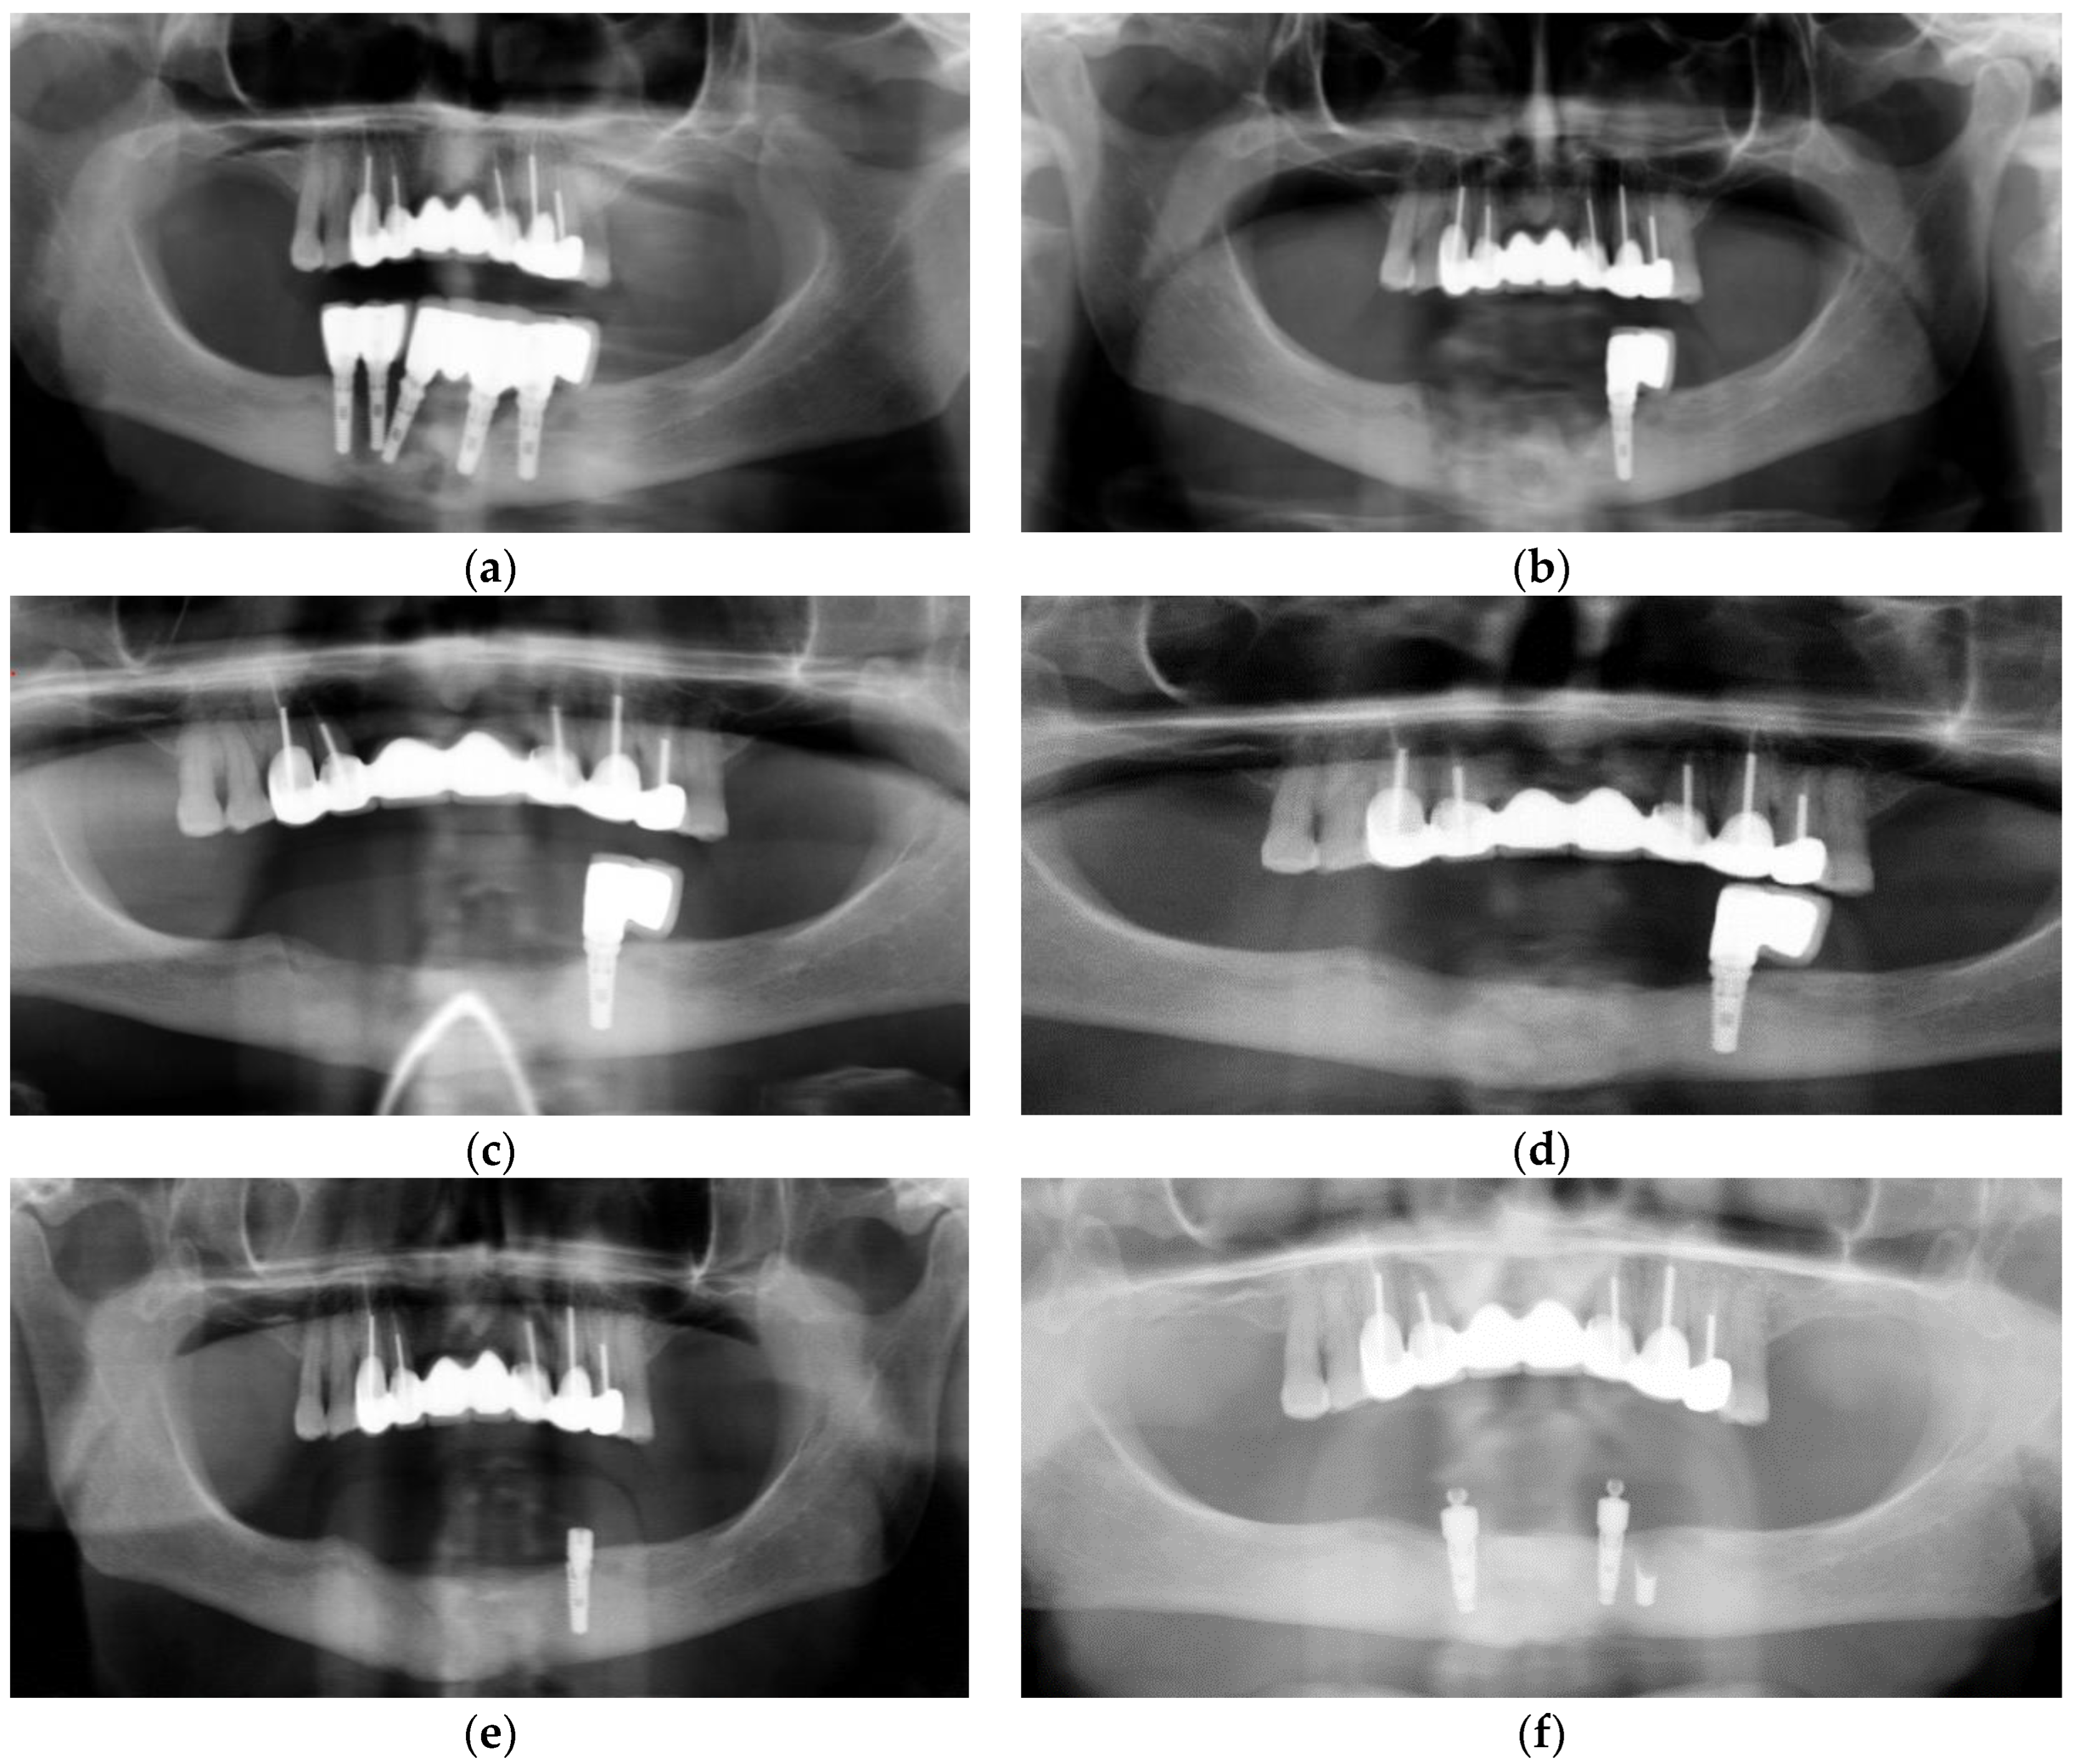

3.1. Case 1

3.2. Case 2

3.3. Case 3

3.4. Case 4

3.5. Case 5